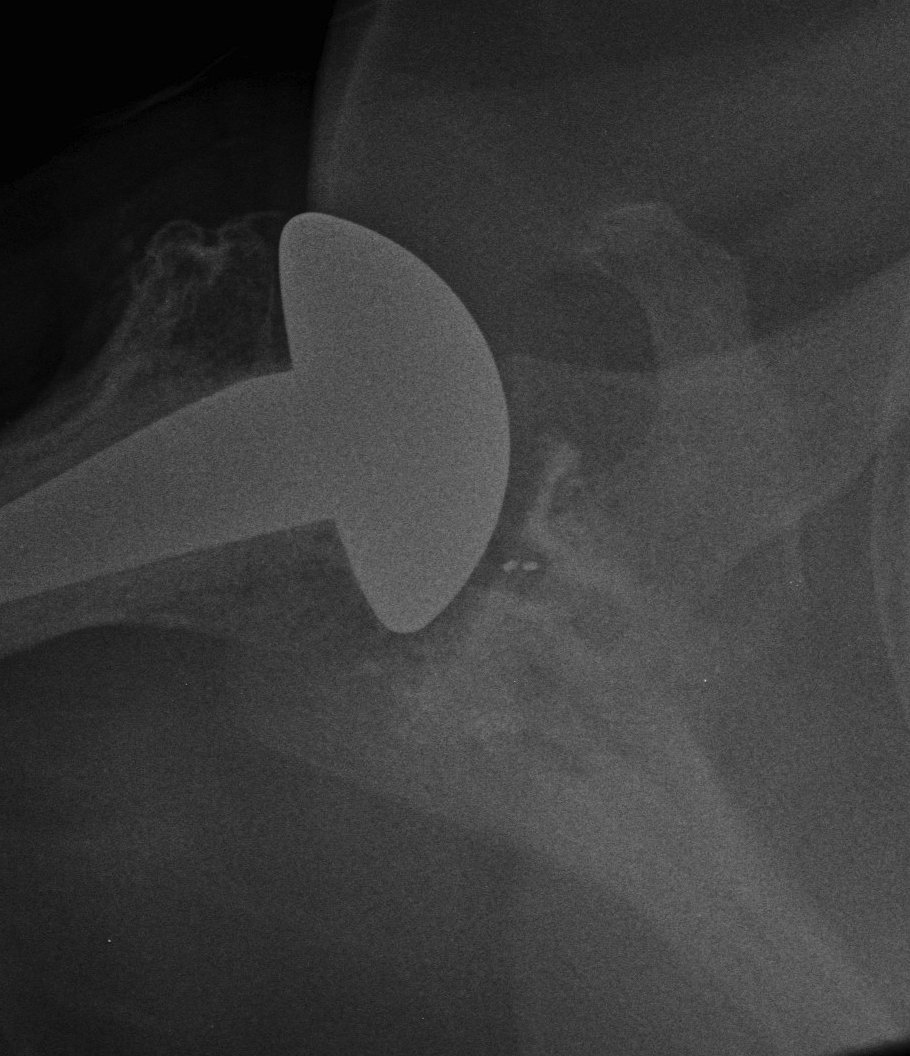

Humeral component

Modern components

Variety of thickness options of humeral head

- overstuffing of joint reduces ROM and places excessive stress on rotator cuff

Offset options

- normal head offset from neck posteriorly and medially

- placing head more anterior than normal can impinge on SSC and cause late rupture

Trial

Should be able to

A. Inferiorly sublux head 50% glenoid and return to center

B. Posteriorly sublux head 50% and return to center

C. Able to close subscapularis without impingement on head